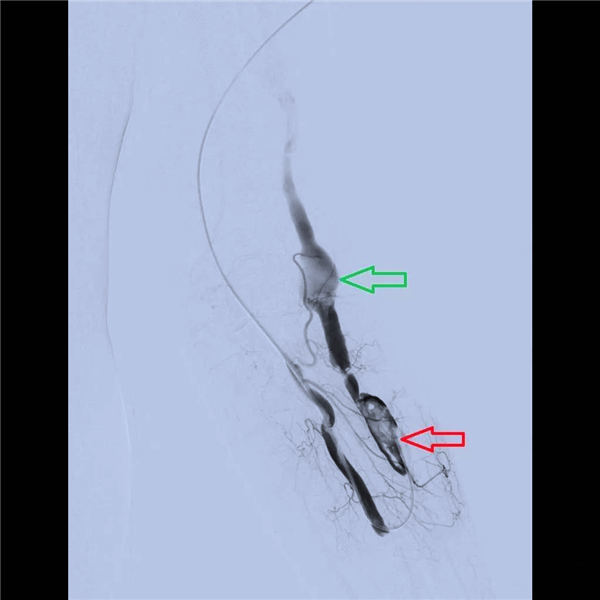

穿刺左侧肱动脉插管后,造影显示(如下图):桡动脉尚通畅,但贵要静脉完全不显影,绿色箭头为闭塞的桡动脉贵要静脉内瘘口,红线为贵要静脉位置。

导管通过闭塞的内瘘口插入贵要静脉,造影显示(如下图):贵要静脉远端(绿色镜头)尚通畅,近瘘口端(红色箭头)局部闭塞、内可见大量血栓,经导管缓慢注射尿激酶溶解血栓。